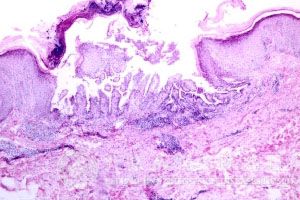

黄水疮的诊断:寻常性黄水疮可根据流行季节、发病年龄、好发部位及典型脓疤等作出诊断。大部分黄水疮患者所表现的特点是比较相似的。大疱性黄水疮及新生儿黄水疮根据其壁薄松弛的大脓疱及强的传染性等不难诊断。能够正确的诊断黄水疮疾病是非常重要的。深黄水疮可分别依据其特有的皮损表现确定诊断。